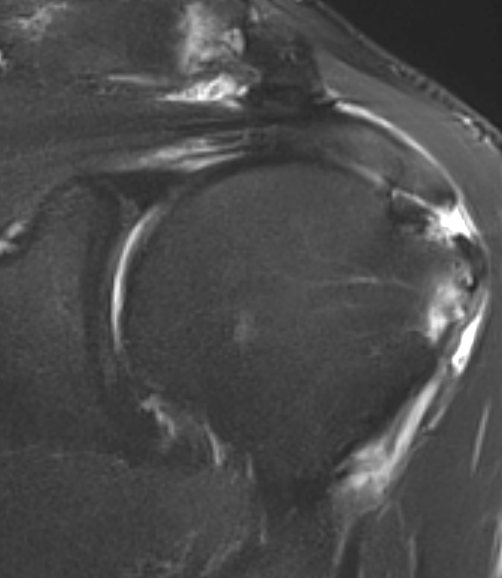

3. Rim rent tear of distal supraspinatus tendon